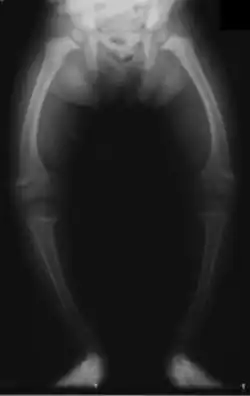

| X-Ray of the legs in a 2 year old child with rickets | |

Genu varum (also called bow-leggedness, bandiness, bandy-leg, and tibia vara) is a varus deformity marked by (outward) bowing at the knee, which means that the lower leg is angled inward (medially) in relation to the thigh's axis, giving the limb overall the appearance of an archer's bow. Usually medial angulation of both lower limb bones (fibula and tibia) is involved.[1]

If a child is sickly, either with rickets or any other ailment that prevents ossification of the bones or is improperly fed, the bowed condition may persist. Thus the chief cause of this deformity is rickets. Skeletal problems, infection, and tumors can also affect the growth of the leg, sometimes giving rise to a one-sided bow-leggedness. The remaining causes are occupational, especially among jockeys, and from physical trauma, the condition being very likely to supervene after accidents involving the condyles of the femur.[2]